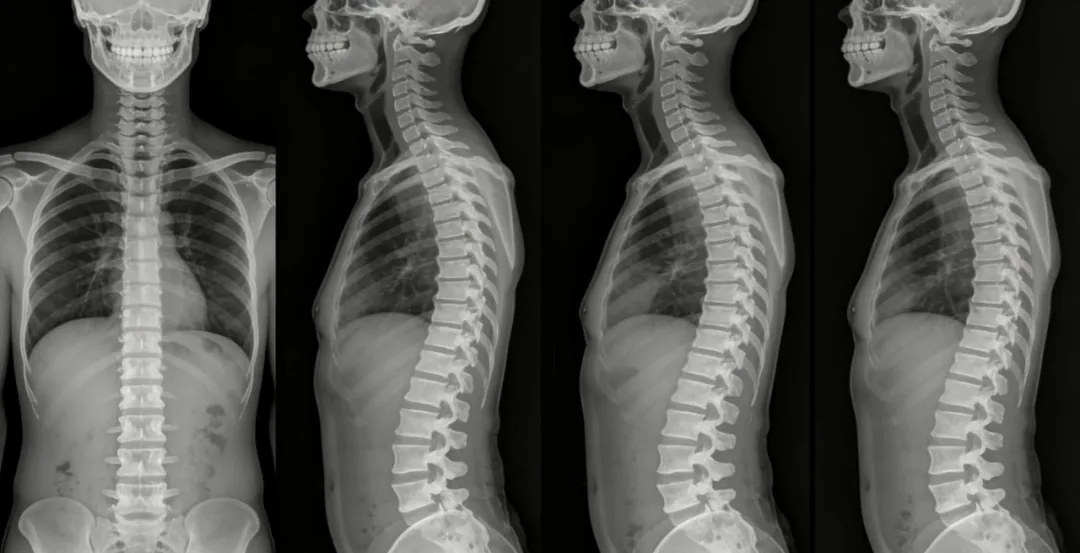

骨科医生拿到你的影像片他在看什么

有经验的骨科医生,从你进门那一刻起就在观察你了。但最准的判断,还是得靠影像片子。

站立位拍一张脊柱的侧位X光片,是查出“体态黑洞”最直接的办法。在这张片子上,医生看的不是“你有点驼背”这种表面现象,而是具体的数据:

别人眼里的一句“就是有点驼背”,在片子上可能已经是各种骨骼角度异常的严重问题了。这不仅仅是习惯不好的问题,而是骨头在长期的错误受力下,真的发生偏位了。